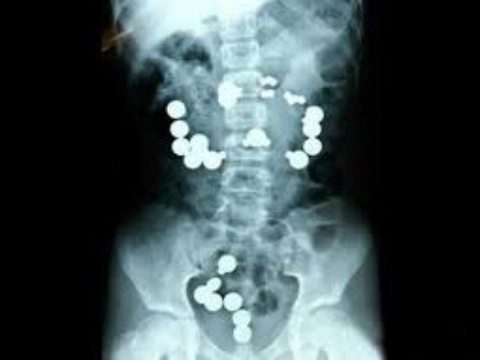

Đặc điểm hình ảnh học Xquang cắt lớp điện toán u mô đệm đường tiêu hóa